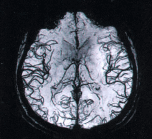

Начальные изменения в мозге, которые сопровождают минимальную мозговую дисфункцию могут быть видны на МРТ. Для этого лучше использовать МРТ с высоким разрешением: МРТ с напряженностью магнитного поля в 1.5 Теслы вполне достаточно. Но при условии наличия в МРТ-аппарате современных программ, которые позволяют с высокой степенью достоверности определять даже минимальные отклонения в мозговой ткани и сосудов.

Отклонения в состоянии сосудов, которые сопутствуют ВСД и вызывают дисфункцию мозга видны при МРТ-реконструкции сосудов головы. Сопоставление сосудистых изменений с изменениями в ткани мозга помогает уточнить диагноз вегетососудистой дистонии (ВСД).

Снимки МРТ реконструкции сосудов головы (выше) без применения контраста. Современные методы диагностики сосудистой патологии головного мозга с использованием современного МРТ оборудования.

Такими изменениями могут быть расширения ликворных пространств (пространства Вирхова-Робина), лейкоореоз или перевентрикулярные свечения тканей мозга, расширение ликворных конвекситальных пространств и ряд других важных для установления диагноза изменений. Такие МРТ находки говорят о запущенном процессе дисфункции мозга. Как правило, причинами этих изменений являются нарушения кровотока в головном мозге в виде ВСД (вегетососудистой дистонии) и сопутствующие нарушения циркуляции ликвора. Читать больше о диагностике ВСД.